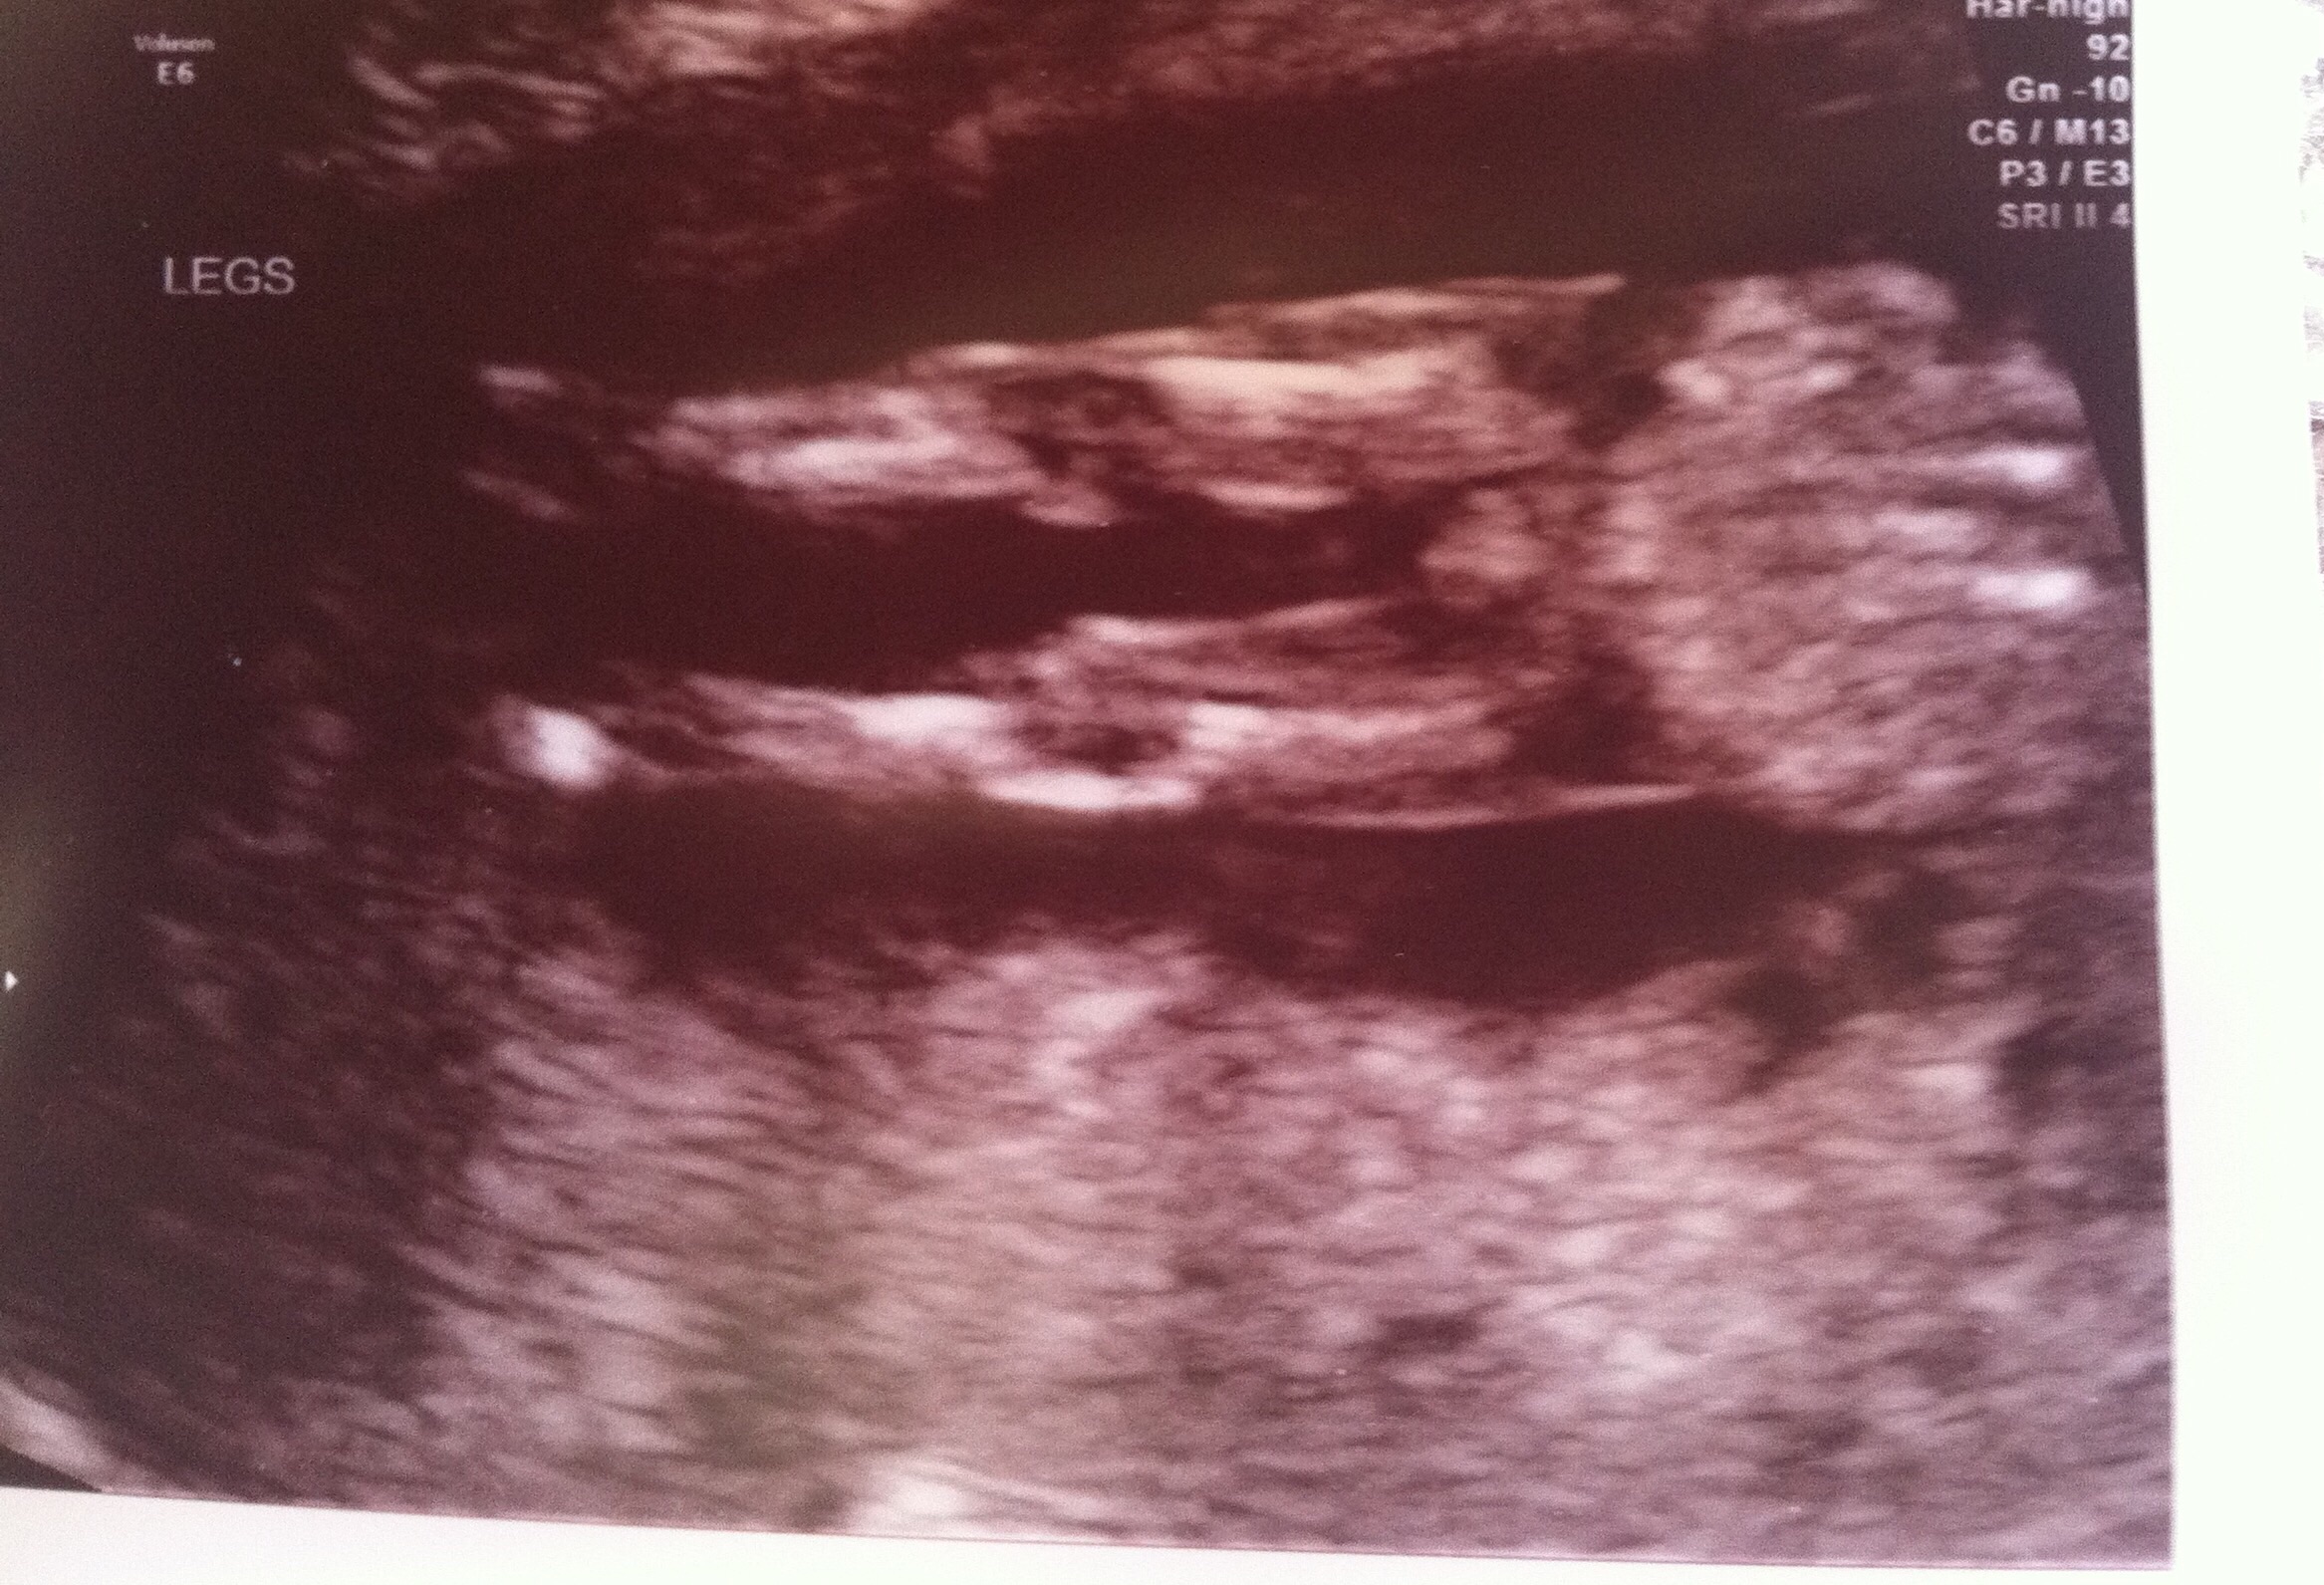

Happy Thursday everyone! I went for my NT ultrasound and blood-work yesterday and during our ultrasound, the Dr. told us she had a prediction on what our baby's gender is that was more than 50% confident. Immediately I thought to myself...it must be a boy (we told her we'd rather her not share her prediction with us since it wasn't 90%+ sure)!

I'll be 13 weeks tomorrow, so yesterday I was 12w5d. What are your thoughts on this? Do you think that her having a prediction this early means that it is a boy? I realize that it could go either way (50/50 always!), but if she felt confident, would it only make sense that she thinks boy?

We'll be finding out for sure at our 20 week ultrasound, but I'm so antsy to know now...would love your thoughts!